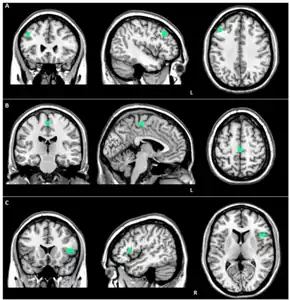

Structural MRI scans often reveal frontal lobe and/or anterior temporal lobe atrophy but in early cases the scan may seem normal. Atrophy can be either bilateral or asymmetric.[26] Registration of images at different points of time (e.g., one year apart) can show evidence of atrophy that otherwise (at individual time points) may be reported as normal. Many research groups have begun using techniques such as magnetic resonance spectroscopy, functional imaging and cortical thickness measurements in an attempt to offer an earlier diagnosis to the FTD patient. Fluorine-18-fluorodeoxyglucose positron emission tomography (FDG-PET) scans classically show frontal and/or anterior temporal hypometabolism, which helps differentiate the disease from Alzheimer's disease. The PET scan in Alzheimer's disease classically shows biparietal hypometabolism. Meta-analyses based on imaging methods have shown that frontotemporal dementia mainly affects a frontomedial network discussed in the context of social cognition or 'theory of mind'.[27] This is entirely in keeping with the notion that on the basis of cognitive neuropsychological evidence, the ventromedial prefrontal cortex is a major locus of dysfunction early on in the course of the behavioural variant of frontotemporal degeneration.[28] The language subtypes of frontotemporal lobar degeneration (semantic dementia and progressive nonfluent aphasia) can be regionally dissociated by imaging approaches in vivo.[29]